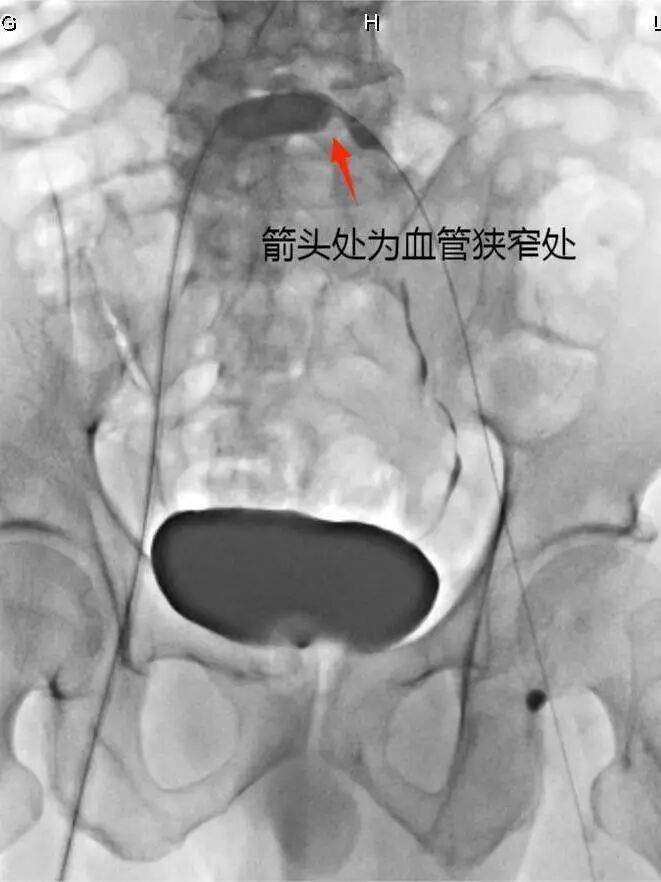

下肢肿胀、下肢疼痛,可能是血管类疾病,严重的可能导致截肢。近日,我院介入科接诊了一例患者,左下肢肿胀,出现皮肤青紫和疼痛,介入科及时开通下肢深静脉血栓,及时挽回了病人濒临缺血坏死的下肢。 患者陈某某晨醒后出现左下肢肿胀,后肿胀逐渐加重,出现了皮肤的青紫及疼痛,遂前往我院急诊就诊,急诊行下肢静脉彩超,发现患者下肢深静脉血栓形成,立即请介入科会诊后收入病房。 手术过程图片:球囊扩张图 介入科副主任医师李志与患者家属沟通,告知家属诊断为急性深静脉血栓形成,股青肿,需要立即进行急诊手术取栓溶栓治疗,否则会有截肢的危险。 事不宜迟,充分术前准备后,介入科立即开始手术,完善下肢静脉造影后,发现患者左下肢静脉内广泛血栓形成,且容易脱落,立即予以患者下腔静脉滤器置入术,防止血栓脱落导致肺栓塞。 滤器释放之后,进行深静脉血栓的抽吸治疗,治疗过程中,发现患者左侧髂静脉存在明显的狭窄,于是对狭窄处进行球囊扩张,球囊扩张之后左下肢的肿胀以及疼痛明显得到缓解,患者左下肢的皮肤颜色也由青紫充血表现慢慢变为了正常。手术非常顺利,患者预后良好,目前已经痊愈出院。 手术前 手术后 据副主任医师李志介绍,股青肿是下肢深静脉血栓最严重的局部表现之一,如不及时开通下肢深静脉血栓,下肢有缺血坏死的可能。陈某某的病例发病急,病情进展快,在介入科全体医护团队的通力协作下,及时挽回了濒临缺血坏死的下肢。 手术中抽吸的血栓 如果患者出现下肢肿胀、下肢疼痛等一系列考虑血管病类疾病时,可前往我院介入科门诊进行咨询了解,门诊时间为每周一、三、四全天。东南大学附属中大医院介入与血管外科副主任邓钢主任医师门诊时间为每周二上午。 专家介绍 邓钢 东南大学附属中大医院 介入与血管外科副主任 主任医师,医学博士,硕士生导师 中华医学会放射学分会介入专委会神经介入组常委 中国医师协会介入医学分会委员 中国医师协会介入医学分会神经介入专业委员会委员 国家脑防委缺血性卒中专业委员会常委 江苏省医学会介入医学分会常委 中国卒中学会复合介入神经外科分会常委 擅长神经系统出血性及缺血性疾病的介入治疗,及外周血管疾病的介入治疗 门诊时间:每周二上午。 何世明 主任医师,溧水区人民医院介入科主任。 中国微创介入治疗委员会委员 江苏省医学会介入分会肿瘤介入学组委员 南京放射介入委员会委员 江苏省中西医放射介入委员 江苏研究型医院肿瘤笑容委员会委员 江苏省肿瘤防治联盟肠癌分会委员 从事肿瘤介入治疗十余年,擅长各种常见肿瘤的介入治疗,发表论文10余篇。 李志 副主任医师,硕士研究生学历,江苏省医师协会介入医师分会妇儿介入学组委员,从事介入诊疗10余年,主要擅长血管性疾病的介入治疗,包括周围血管狭窄、闭塞性疾病的血管成形术,动静血栓形成的消融治疗,急性出血性疾病的栓塞止血等,肿瘤的综合介入治疗,如肿瘤血管药物灌注与栓塞,恶性梗阻性黄疸的减黄治疗等,以及下肢静脉曲张的微创介入,静脉输液港置入等。